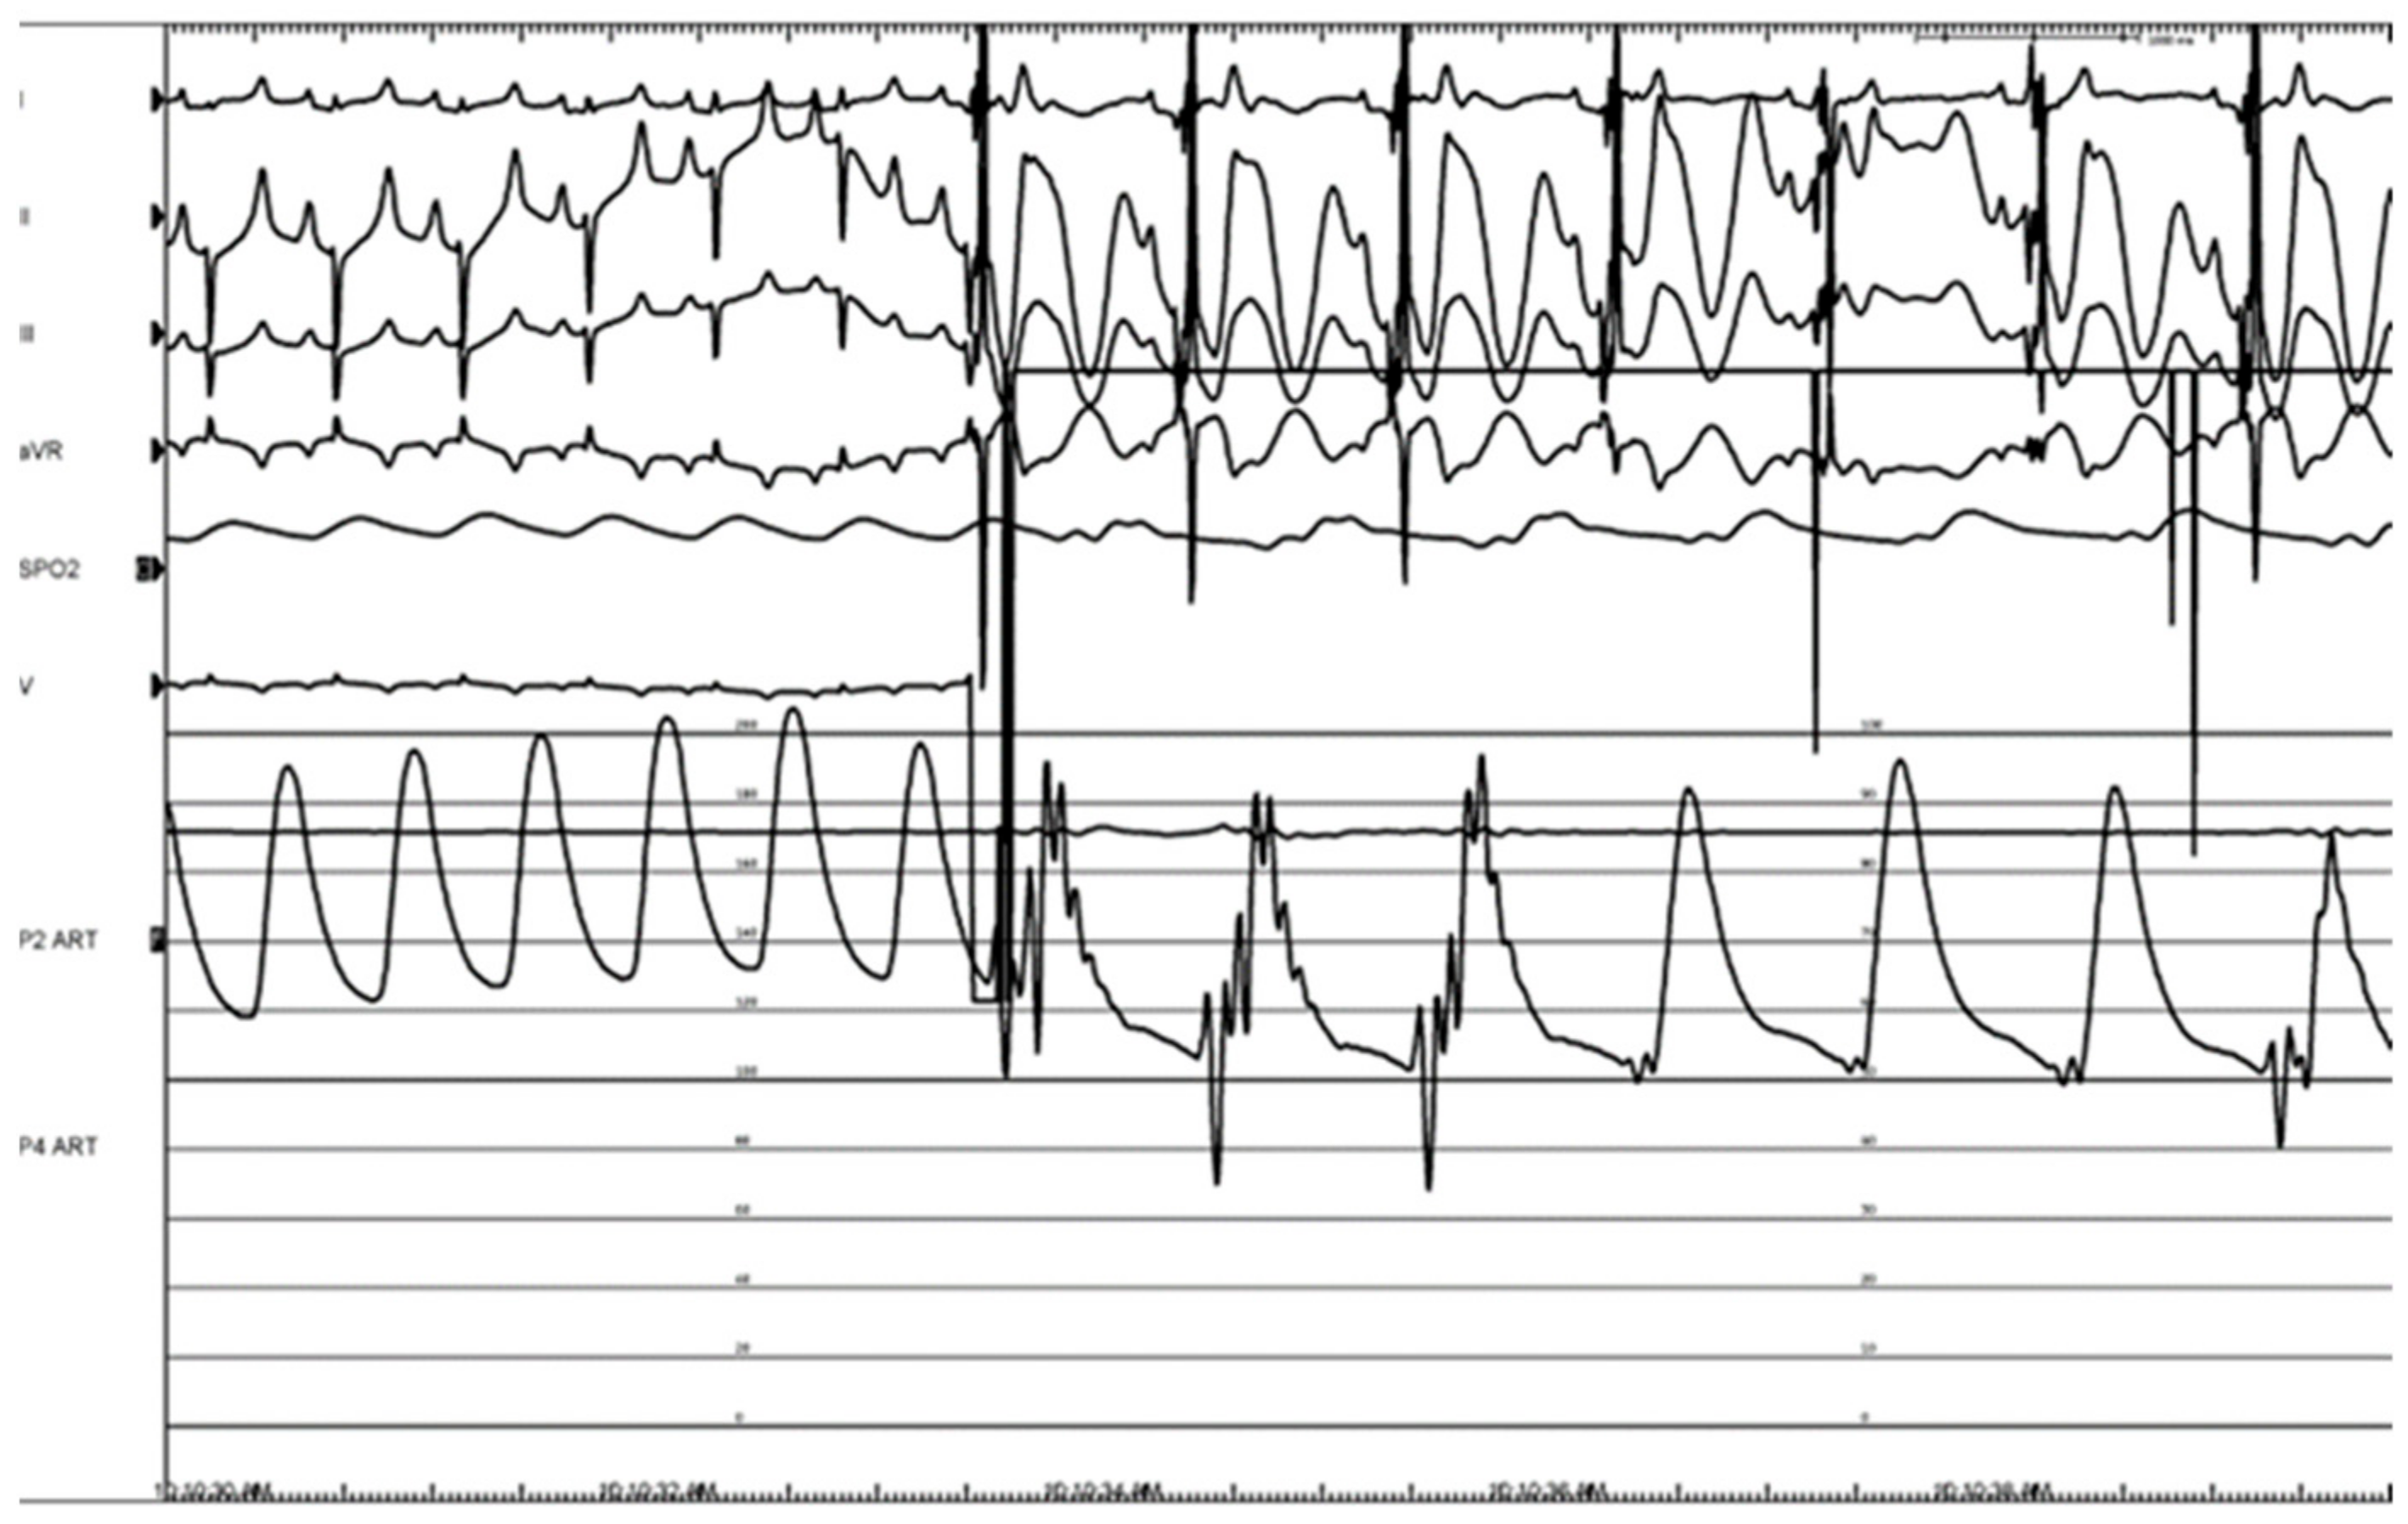

3.3. Histologic Evaluation

- Pachon M, J.C.; Pachon, E.I.; Santillana, T.G.; Lobo, T.J.; Pachon, C.T.C.; Pachon M, J.C.; Albornoz, R.N.; Zerpa, J.C. Simplified Method for Vagal Effect Evaluation in Cardiac Ablation and Electrophysiological Procedure. J. Am. Coll. Cardiol. EP. 2015, 1, 451–460. [Google Scholar] [CrossRef] [PubMed]